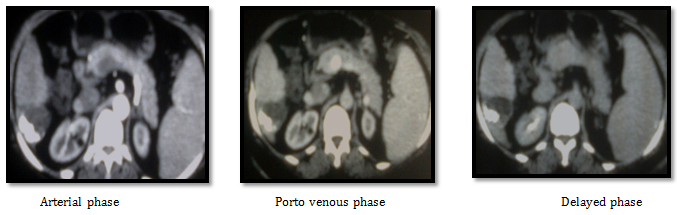

Case number (2): A 50years old male patient known to have hepatitis C virus with right hepatic lobe HCC of about 5.5 cm by triphasic CT scan. His laboratory tests was as follow AFP 6.3 IU/ML, ALT 94, AST 72, Direct Bilirubin 2, Albumen 3.2g/dl, Creatinine 0.9) with normal CBC , PC 65%, INR 1.3).

CT images before doing any procedure: His CT showing right hepatic lobe segment VIII well defined focal lesion of about 5.5cm very close to the right portal vein branch with early nodular enhancement in arterial phase and rapid wash out in delayed phases, mild splenomegaly and no ascites. We decided to start by RF ablation (Figure 7).

Figure 7 CT Images before doing any procedure.

CT images after three weeks from RF ablation: Post RF CT showing partial about 50% ablation of the lesion with residual tumoral reactivity and newly developed intra-lesional portal shunts. Then we decided to complete treatment by TACE after one month from RF ablation. 1st we did angiography that revealed right hepatic artery superior branch small aneurysmal dilatation (pseudo-aneurysm), that is appears after RF ablation. It was affecting the flow as seen in next images (Figure 8). So we decided to embolize the aneurysm and correct the flow into the tumoral tissue as seen in the following images (Figure 9). Lastly we injected the chemo-lipiodol mixture into the right lobe lesion (Figure 10).

Figure 8 CT Images after three weeks from RF ablation.